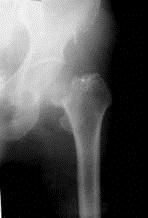

病历摘要: 患者××,女性,70岁,不慎跌倒致伤左髋部后疼痛、活动障碍2天。查体:左下肢呈屈髋屈膝及外旋畸形,右下肢活动时左髋部疼痛,左足跟和大粗隆有叩击...

问题 病历摘要: 患者××,女性,70岁,不慎跌倒致伤左髋部后疼痛、活动障碍2天。查体:左下肢呈屈髋屈膝及外旋畸形,右下肢活动时左髋部疼痛,左足跟和大粗隆有叩击痛。 为了预防人工髋关节置换术后发生感染,以下措施哪些是对的?